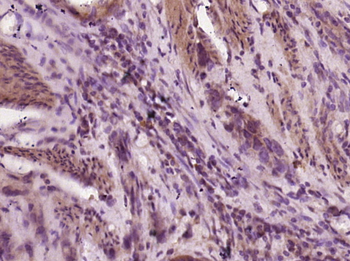

Gastrin Releasing Peptide Rabbit Polyclonal Antibody抗体

Gastrin Releasing Peptide Rabbit Polyclonal Antibody

GRP

IF, IHC-Fr, IHC-P

KLH conjugated synthetic peptide derived from human GRP (24-50/148aa)

免疫原:KLH conjugated synthetic peptide derived from human GRP (24-50/148aa)

应用稀释比例:IHC-P=1:100-500, IHC-F=1:100-500, IF=1:100-500